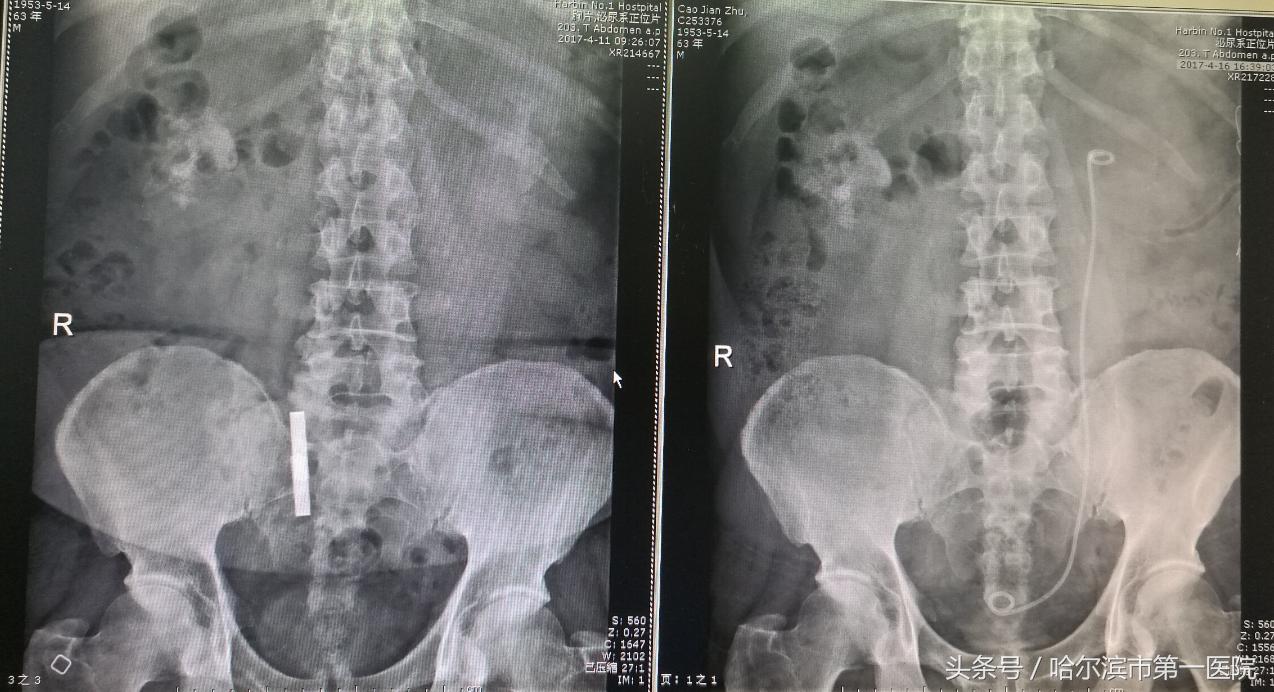

铸型结石术前与术后X线对比

检查中发现,曹先生的结石最大径线45×36mm,像一个“鹿角”一样,已经塞满了左侧肾盂和各个肾盏。经过术前讨论后,具有多年微创碎石取石经验的哈尔滨市第一医院泌尿外科专家孙长华主任采取了“经皮肾镜超声碎石取石”的治疗方案。术中通过用超声在左侧后腰精准定位,然后打一个直径约0.8公分的通道,用超声弹道碎石系统击碎结石,并将碎石吸出体外,仅用半个小时,就彻底清除巨大结石。术后复查,无结石残留,6天后病人痊愈出院。